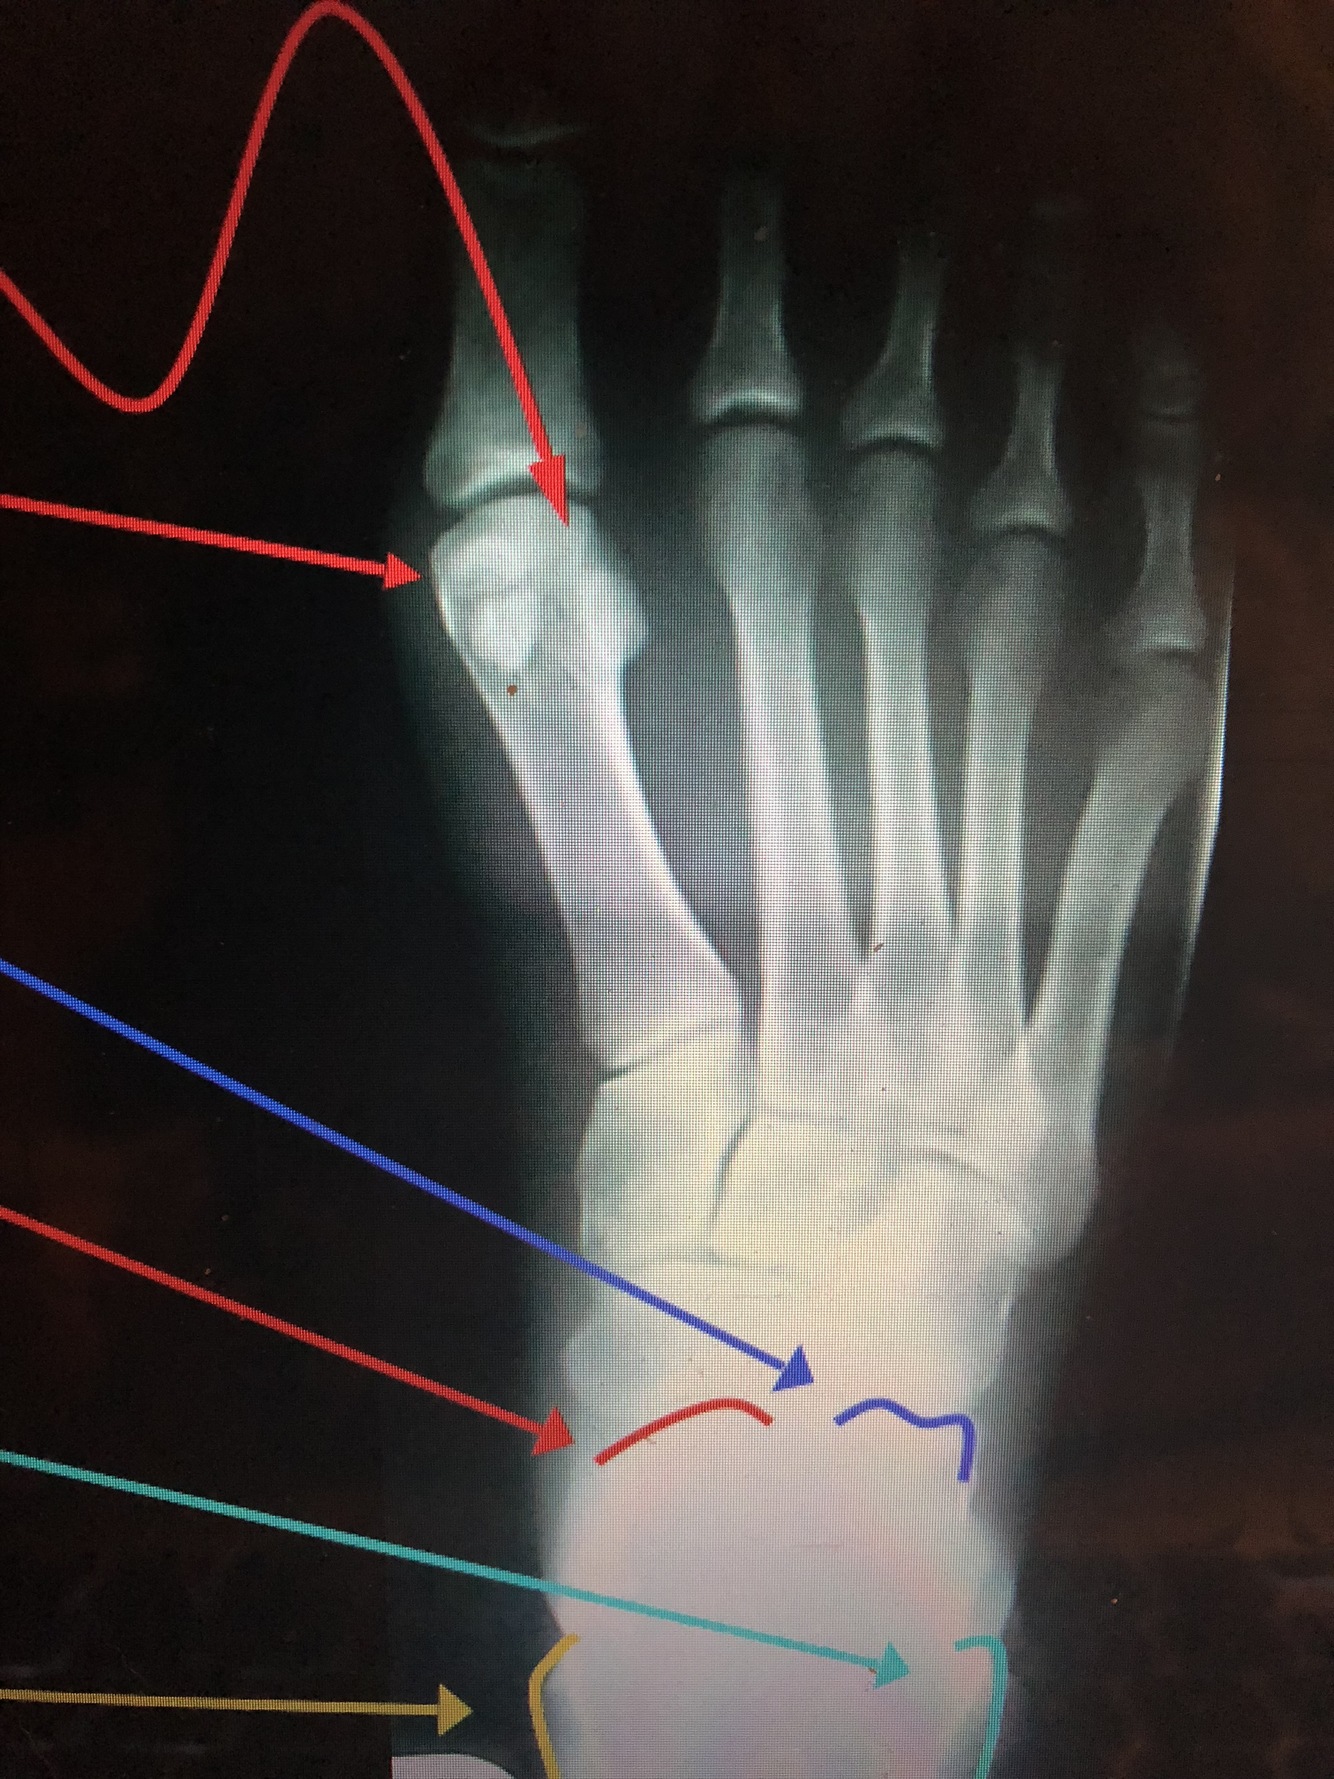

What are the top two red lines?

Sesamoid Bones

•Found in the tendon of the flexor hallucis brevis

What bone is dark blue?

Calcaneus

What bone is the bottom red line?

Talus

What is the light blue lines?

Lateral Malleolus

What is the yellow line?

Medial Malleolus

Which phalange is which color?

Dark blue - distal second phalange

Red - middle second phalange

light blue - proximal second phalange

What part of the phalanges are what color?

red - head of second phalange

dark blue - base of second phalange

light blue - Distal Ungual tuft